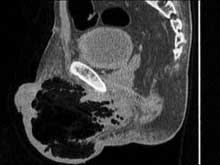

气性坏疽

(气性坏疽病、梭菌性肌坏死、梭状芽孢杆菌性肌)

检查

X线平片、病原体检测、活体组织病理检查(活检)